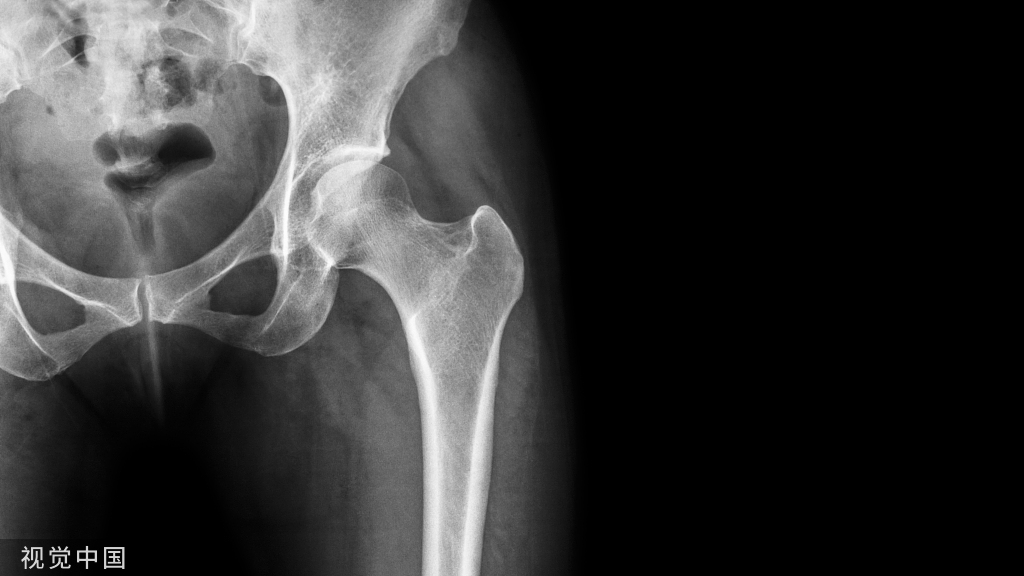

骨质疏松症是一种常见的老年退化性疾病,老年人和女性是患骨质疏松症的主要人群,和骨关节炎一样都会表现为骨痛,但骨质疏松引起的疼痛一般是全身骨骼痛,且往往是持续的。

骨关节炎好发于50岁以上人群,女性多于男性,可发生于全身各个关节 ,但更好发于负重较大的膝关节、髋关节、脊柱等,主要表现为关节开始活动时疼痛明显,稍活动后疼痛减轻,而当负重较多或关节活动过多时,疼痛又会加重。

有时,疼痛可呈放射性,骨关节炎患者在发病早期会出现关节僵硬、关节不稳、关节屈伸活动范围减少及步行能力下降等。骨头疼有可能是骨质疏松,还有可能是骨关节炎。